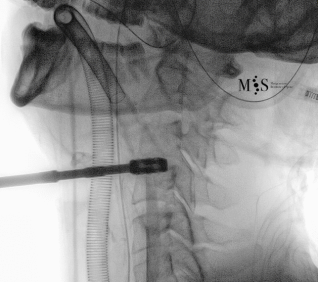

Images showing the endoscopic placement of a cage into a cervical disk

Animated image showing the endoscopic insertion of an intervertebral cage into a cervical disk.

Note the distraction of the disk space during as the cage is inserted.